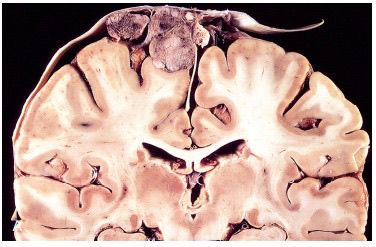

Meningiomas are relatively benign tumour of meninges that arise from the meninges and to be more specific from the arachnoid meningothelial cells. Slow growing tumours found in adults. They can grow along the outer surface of the brain or may be found in the ventricular system. Menongiomas can be graded into three grades: Grade l: Well-differentiated tumours that do not invade Grade ll: Atypical meningiomas that are locally aggressive and have a higher recurrence rate. Grade lll: Anaplastic (malignant) are high grade tumours that are typically fast growing. Picture credit: Robbins and Cotran pathologic basis of disease (10 edition)